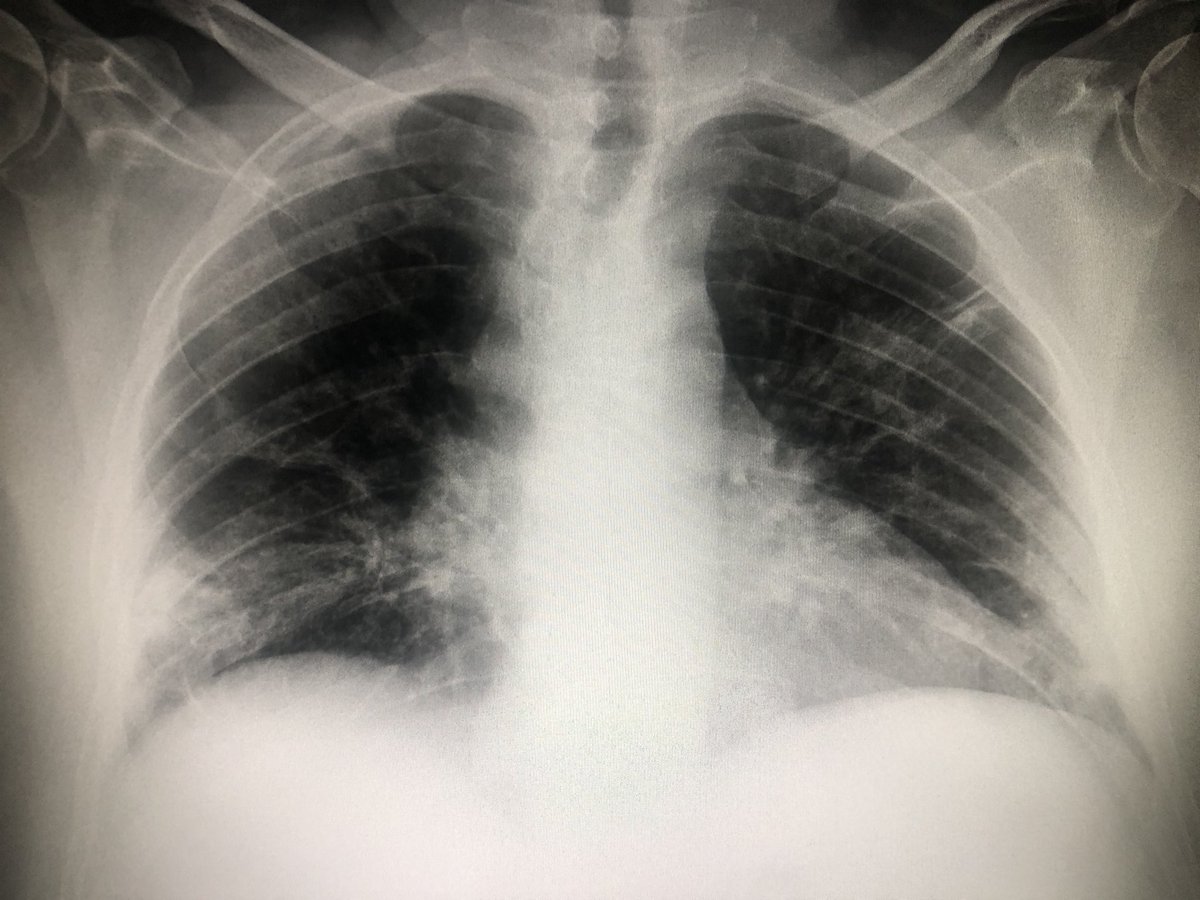

Pacient de 56 anys, hipertens. Al 2n dia de febre i tos, radiografia neta. Covid Positiu. 5 dies despres, pneumònia bilateral, i distrés respiratori. Contagi en entorn familiar. No és cap broma. #COVID19 #salut #Lleida

oyuguero's tweet image. Pacient de 56 anys, hipertens. Al 2n      dia de febre i tos, radiografia neta. Covid Positiu. 5 dies despres, pneumònia bilateral, i distrés respiratori. Contagi en entorn familiar. No és cap broma. #COVID19 #salut #Lleida